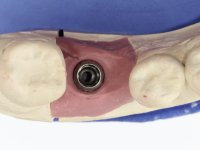

Após 5 anos da primeira intervenção, a paciente surge na consulta com uma peri-implantite nos implantes colocados no local dos dentes 1.2 e 4.6. Começamos por abordar a peri-implantite no local do dente 2.2. Foi feita uma ponte provisória de laboratório em acrílico com 2 elementos. O dente 1.1 como pilar e o 1.2 como pôntico, este último apresentava um apoio distal. A coroa do 1.2 foi removida do coto com um corte longitudinal feito com turbina e depois foi fraturada com um mini luxador. O coto foi de seguida desaparafusado do implante. Fez-se o mesmo procedimento para remover a coroa do 1.1. O dente 1.1 foi re-preparado e a ponte provisória foi rebaseada em boca com acrílico autopolimerizável. Feito o correto acabamento e polimento da provisória foi feita a sua cimentação temporária com cimento de policarboxylato. Numa consulta posterior. foi feita a remoção da ponte provisória, feita a cirurgia para explantação do implante, colocou-se um novo implante e fez-se a regeneração óssea da zona com uma membrana não reabsorvível. 3 meses após foi removida a coroa do implante colocado no 4.6. Foi feito um corte horizontal com turbina na zona cervical e com um mini luxador descolou-se a coroa do coto. Após este procedimento fez-se a explantação do implante. Após 6 meses foi colocado um novo implante no local do 4.6. Após a osteointegração foi feita a impressão com a técnica de moldeira aberta e foi confecionada em laboratório uma coroa aparafusada sobre o implante. Aprovada pela paciente foi apertada definitivamente em boca. Após 1 mês removemos a ponte provisória antero-superior, reforçamos o dente 1.1 com um poste intra- radicular e reconstruimos o coto com uma resina de polimerização dual. Nessa mesma consulta expomos o implante colocado no 1.2 e fizemos uma impressão pela técnica de moldeira aberta com silicone de dupla viscosidade e presa rápida. No laboratório foi feita uma ponte provisória de 2 elementos, aparafusada sobre o implante e cimentada sobre o dente. A primeira ponte provisória foi removida e colocada a segunda aparafusada sobre o implante. A linha de acabamento cervical do 1.1 foi rebaseada com resina composta durante o aperto do parafuso do implante. Depois foi removida, foram feitos os acabamentos e finalmente apertada sobre o implante e cimentada temporariamente sobre o dente. Após 2 meses de maturação dos tecidos moles em função do perfil de emergência criado pela nova ponte provisória, pudemos avaliar a estética conseguida em conjunto com a paciente. Neste longo processo o dente 2.1 teve que fazer um tratamento endodôntico. Decidiu-se assim fazer também uma coroa no dente 2.1.O dente 2.1 foi preparado na mesma consulta em que se fez a impressão ao implante. A ponte provisória foi utilizada para individualizar a peça de transferência, copiando o seu perfil de emergência e em seguida foi realizado o afastamento gengival com caolino. A impressão foi feita com a técnica de moldeira aberta com silicone de dupla viscosidade e presa rápida. Após a escolha da cor, a impressão foi enviada  para o laboratório onde foram confecionadas 2 coroas  com infraestrutura em Zr. revestidas a cerâmica para os dentes 1.1 e 2.1 e uma coroa aparafusada sobre o implante no dente 1.2. O trabalho final foi aprovado pela paciente e foi colocado definitivamente em boca. A coroa sobre o implante foi aparafusada com 35 N e as coroas foram cimentadas com cimento de ionómero de vidro reforçado com resina.